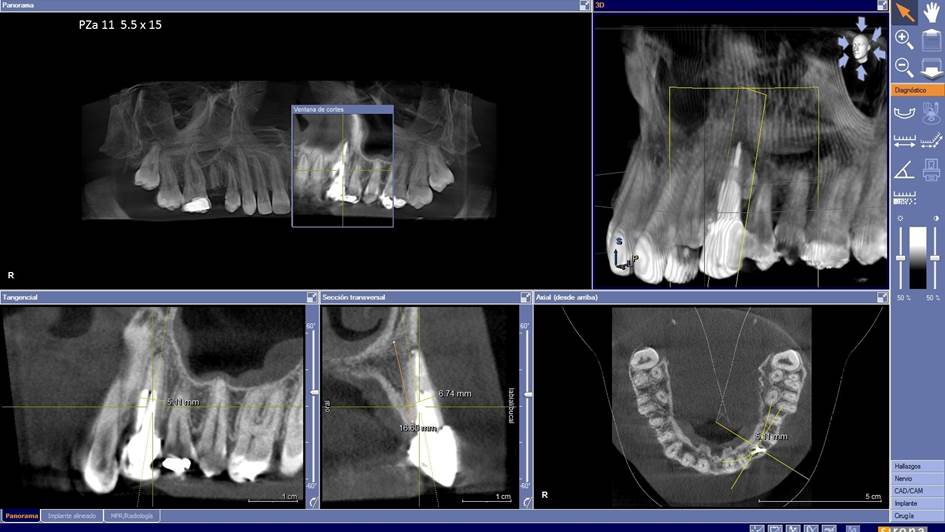

Clinical case: Digital Data Save concept in upper jaw premolar area

- Courtesy of Dr. Lysov Alexander Dmitrievich & Dr. Sofronov Matvey Vitalievich, Russia -

Keywords

AnyRidge, R2GATE, R2GATE guide, ISQ value, initial stability, immediate loading, KnifeThread, maxillary posterior, #14, Digital, Dr. Lysov Alexander Dmitrievich, Dr. Sofronov Matvey Vitalievich, zirconia abutment, CAD/CAM crown

“AnyRidge & R2GATE show stable results

after immediate extraction, immediate implant placement, & immediate loading,

even with low bone density.”